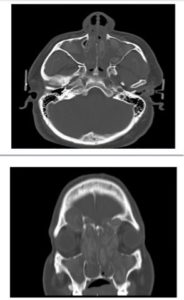

Allergic Fungal Sinusitis CT ScanHowever, for patients with more extensive disease, Clazon Martin CT scan (on right), such as the patient whose CT scan saw his disease was so extensive that the polyps were causing his Left eye to bulge out, oral or intravenous antifungals may be necessary.  This should not be taken lightly and should be managed by someone such as an infectious disease specialist to be done safely.  Once these more severe cases improve most likely they’ll have to go on aerosolized therapy afterward.